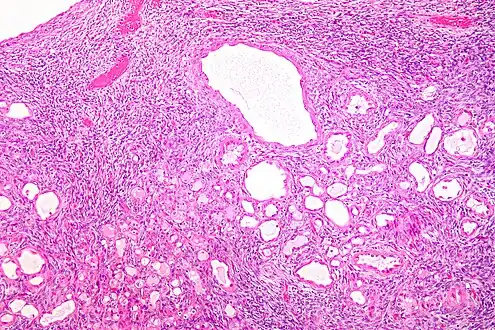

| Micrograph of a cystic nephroma (left of image). Normal kidney is seen on the right. H&E stain. | |

A cystic nephroma, also known as multilocular cystic nephroma, mixed epithelial stromal tumour (MEST) and renal epithelial stromal tumour (REST),[1] is a type of rare benign kidney tumour.

Micrograph of a cystic nephroma. H&E stain.

The characteristics of cystic nephromas are:

- Cysts lined by a simple epithelium with a hobnail morphology, i.e. the nuclei of the cyst lining epithelium bulges into the lumen of the cysts,

- Ovarian-like stroma that has a:

- Spindle cell morphology, and has a

- Basophilic cytoplasm.